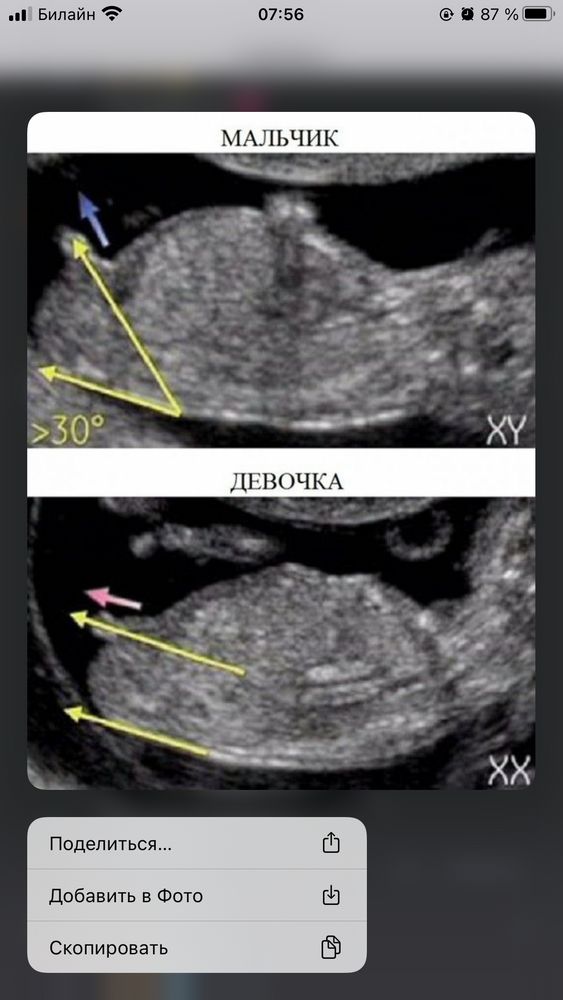

По наклону полового бугорка явно девочка

На этом фото явно девочка)

На этом фото больше на девочку похоже.

Мне тоже кажется, что девочка